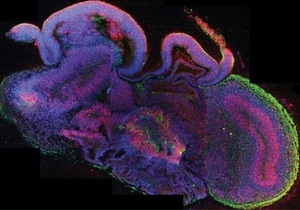

Новини науки - мозок: Австрійські вчені виростили подобу мозку

Фото: nature.com

Штучні "органоїди" можуть стати в нагоді для вивчення вроджених порушень розвитку

Вчені з Австрії виростили зі стовбурових клітин "органоїди" нервової тканини, що нагадують мозок, пише журнал Nature.

Клітини-"заготовки" виростили на спеціальній синтетичній гелевій підкладці, а потім перенесли в обертовий біореактор, де вони дозрівали і диференціювалися, формуючи згустки нервової тканини.

Нервові згустки мали складну будову і демонстрували деякі властивості справжнього мозку. Крім того, нервова тканина в них була організована в шари, які нагадували кору мозку. Під час дозрівання нейрони мігрували з одних відділів" органоїда" в інші - точно так само, як це відбувається під час формування нормального мозку.

Втім, на відміну від нормального органу, "органоїди" у великому масштабі мали неправильну, випадкову структуру. Також у них були відсутні кровоносні судини, що сильно обмежувало їхній розмір.